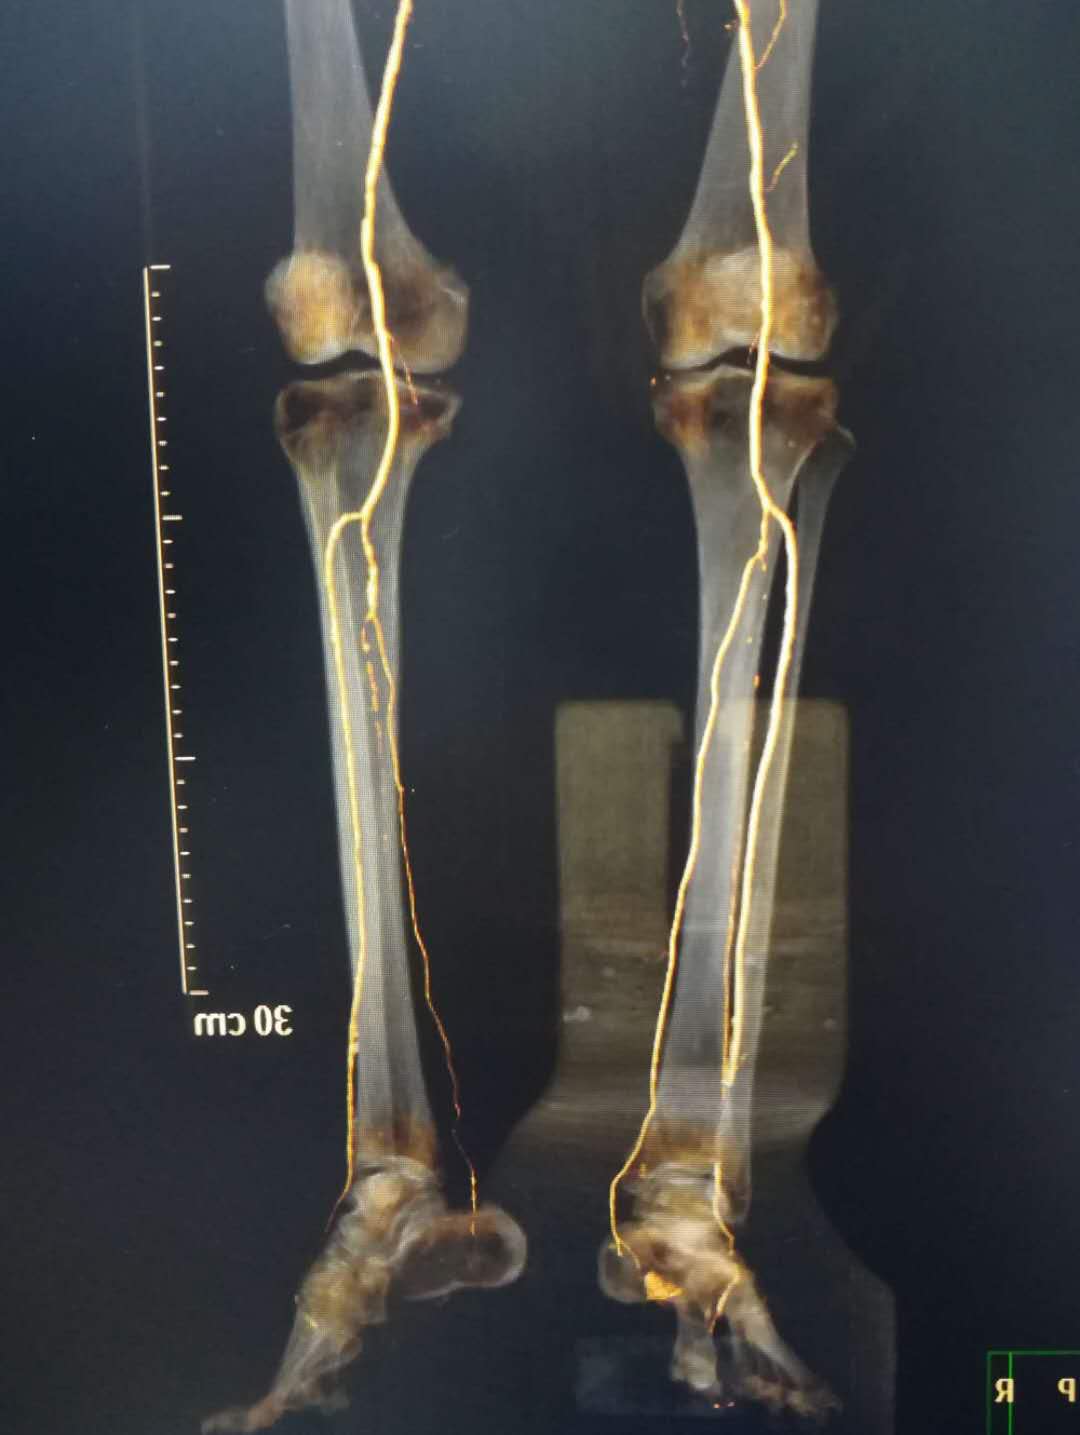

骨搬运手术前,微血管稀疏

骨搬运手术后,产生大量的新生血管网

搬运前血管稀疏

搬运后血管网密集